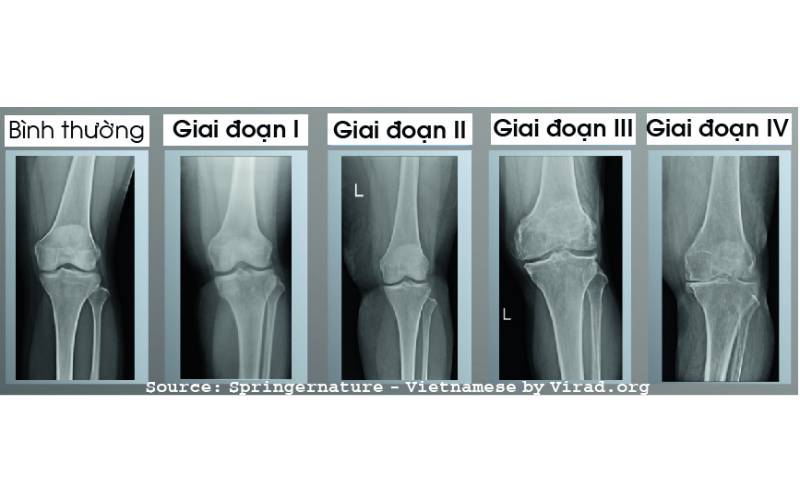

Hình ảnh trên phim chụp Xquang của bệnh thoái hóa khớp gối.